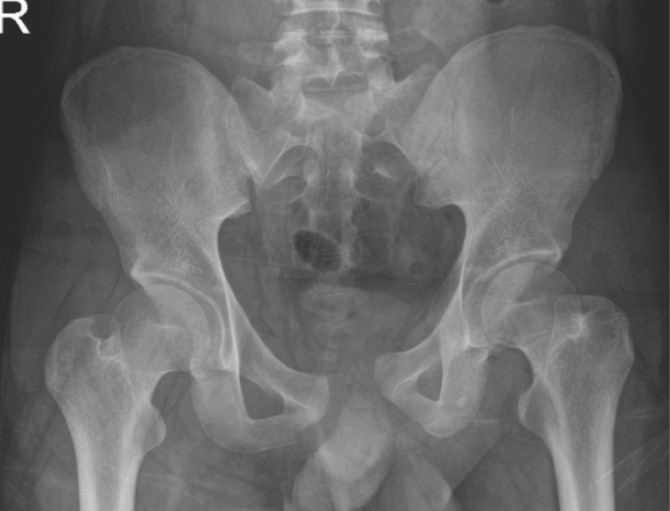

Introduction: Sacroiliac joint disruption, resulting from high energy trauma can cause significant morbidity if no proper treatment given. Many techniques can be used to stabilise pelvic ring injuries. We studied the functional and radiological outcome following open reduction and anterior fixation of the sacroiliac joint and agreement between both outcomes.

Material and methods: This retrospective study involved 15 patients with unstable pelvic injuries requiring surgical intervention from January 2015 to December 2020 who undergone anterior stabilisation of the sacroiliac joint. Radiological outcome assessments were done postoperatively by using Lindahl criteria. The complete functional outcome was assessed at least six months postoperatively when patients were able to weight bear by using Majeed system. Descriptive statistical analysis was performed using IBM SPSS Statistics Version 27.

Results: The participants consist of 73.3% male and 26.7% female patients. A total of 66.7% of patients had a Tile type B pelvic ring injury, and the remaining 33.3% had a Tile type C pelvic ring injury. Based on the Majeed system, 73.3% of patients had excellent functional outcomes, and based on Lindahl criteria; there were 60% of patients who had excellent radiological outcome. However, there was no significant agreement between functional and radiological outcomes.